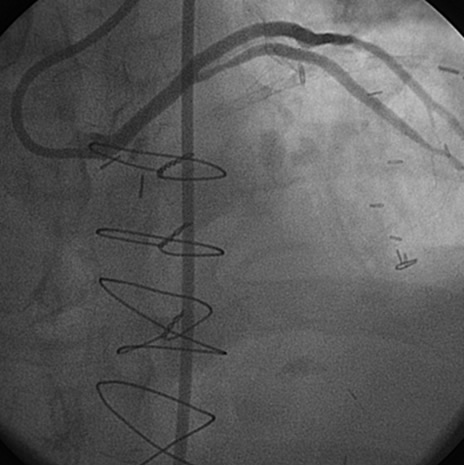

In the past, surgeons used rings to mark the ostia of the vein grafts substantially aiding the angiographer to localize the vein graft ostia during angiography. However, nowadays, it is not a usual practice. The lack of marker can increase the contrast use and radiation particularly in patients without the knowledge of the types and number of vein grafts. As mentioned earlier, right coronary grafts have usually a right sided take off from the aorta. Therefore, using standard view, left anterior oblique (LAO), which is used for right coronary artery catheterization is the view of choice. Left coronary bypass grafts have usually anterior take off. Therefore, a right anterior oblique (RAO) makes it easier to engage the left-sided vein graft ostia preventing foreshortening of the catheter tip. Using RAO, the catheter tip should be oriented to the right side of the screen. The vein grafts to the left system is based on the anatomical proximity of the native coronary to the aorta. Therefore, LAD graft ostia are usually closest grafts to the aortic valve followed by diagonal and circumflex grafts. Circumflex graft ostia usually have the highest take off from the aorta. There are occasional cases with different take off making vein graft angiography difficult. In such a situation, the angiography catheter has to be probed across the aorta in different level in order to engage the ostial vein graft. A non-selective strong contrast injection or aortogram may be necessary to delineate the unusual take off of missing vein grafts or documenting total occlusion of missing vein grafts. Total occluded vein grafts usually have a residual knob in the aorta that can be seen during angiography.

The most commonly used catheters for left heart catheterization and vein graft angiography can be seen in Figure 1 and Figure 4-13. Most of the vein grafts have horizontal take off and can be successfully engaged using a commonly used Judkins right number 4 (JR4) catheter. The JR4 catheter is the most commonly used catheter for the engagement of the right coronary ostium with horizontal take off. However, many vein grafts have unusual take off requiring different catheters. Many right coronary vein grafts have steep inferior take off making the ostial engagement with JR4 difficult or impossible (Figure 10). In such a scenario, a multipurpose catheter which has a shallow angulation is the best choice (Figure 11). The second major challenge in engaging vein graft ostia, particularly vein grafts supplying the left coronary arteries, is the shape of the aorta. A large aorta can make it very difficult for the JR4 catheter to reach the ostial vein grafts. In such a situation, Amplatz (AR) right and left (AL) catheters can be very helpful to reach the vein graft ostia. Amplatz catheters have a larger primary curve and have been used successfully in unusual superior take off of left coronary arteries or vein grafts and in large aorta. Amplatz catheters are available in different sizes (from smaller to larger curve: AR 1, AR2, AL2, AL2 and AL3). Occasionally, a very superior take off of a vein graft requires specially designed bypass graft catheters. Amplatz catheters are also extremely helpful in engaging native right coronary ostium with anterior take off.